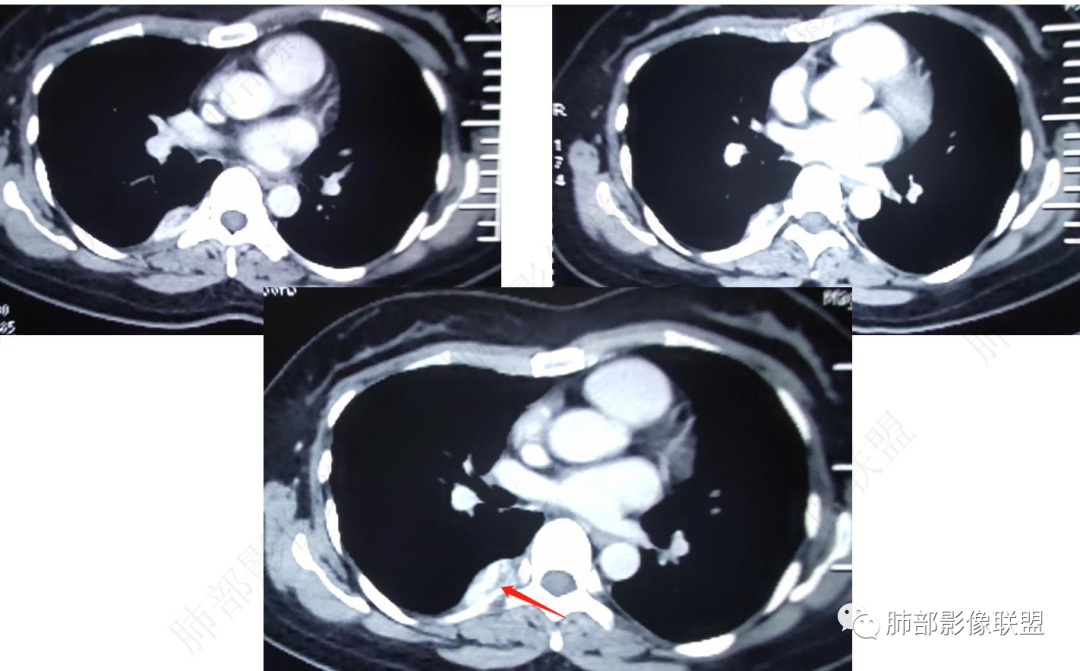

CT表现: 大多数病灶呈境界清楚的肿块影,呈蔓状生长,质地软,仅少部分与周围结构分界不清,平扫时肿块密度均匀或不均匀,肿块内可见小点状钙化、静脉石或血栓形成,偶尔可见脂肪密度影,增强后强化方式多样,呈典型的多灶性或弥漫性不均匀性强化,也可呈中心型或外周型强化,肿块内也可见强化的血管腔,在动脉期即能显示与纵隔大血管一样的强化。

中青年女性,胸痛就诊,CT检查发现右后纵隔占位,病灶位于后胸壁纵隔移行区,略呈卵圆形或梭形蔓延,质地软,等/稍长T1、显著长T2信号,T2W脂肪抑制序列“亮灯”样高信号,这种磁共振信号特征对血管瘤具有强烈提示意义!(实在是太亮了,严格意义上的肿瘤罕见)

病灶显著强化,强化与纵隔大血管相仿且同期,一般会提示是血管源性病变,如血管瘤,如果边缘结节样强化逐渐填充渐进,则提示可能为海绵状血管瘤。